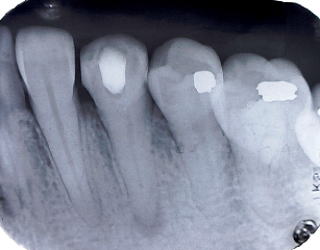

である。開業当初から当診療システムで38年間口腔管理をしている。Panorama、CTなどレントゲンを介しての顎骨・歯槽骨の形態・骨

量などを観察したもので、歯槽骨の吸収状態から診ても、ほぼ二十歳代に相当するように思われる。過去の論文を見ても、口腔内写真

(図15)2015年7月27日、83歳。高年齢と残存歯数ばかりが問題視されているが、歯槽骨の状態、歯肉、Pocketの状態を含めた歯周病を評価すべきである

歯周病治療38年経過:83歳(女性)残存歯数28本